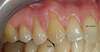

Cas°5 Récession multiples traitées par greffe de gencive